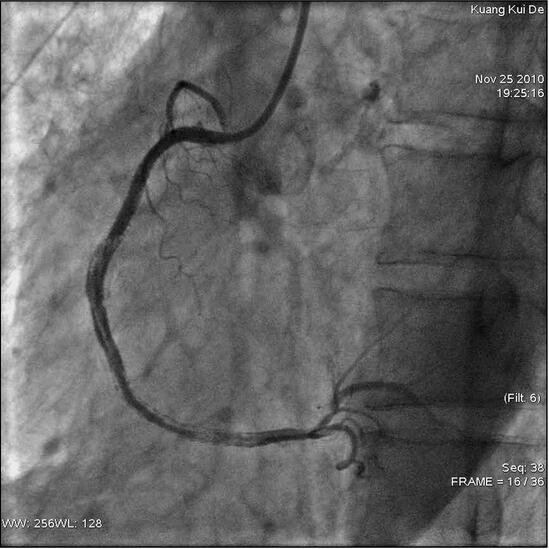

图97‐1 右冠中段喷射性冠脉穿孔

患者男性,66岁,因反复发作性胸痛1年,加重2天入院,既往有高血压、糖尿病及慢性支气管炎病史。入院查体:意识清楚,脉搏73次/分钟,BP120/65mmHg。双肺呼吸音清,心率73次/分钟,律齐,心音低钝。心电图示:下壁导联ST段弓背向上抬高0.1~0.2mV,入院后查CK‐MB及肌钙蛋白T定量均升高但呈下降趋势,诊断冠心病,急性下壁心肌梗死,心功能Ⅰ级,高血压病3级(极高危),2型糖尿病。入院常规冠心病药物治疗1周后经桡动脉行冠脉造影显示,右冠状动脉中远段弥漫性钙化病变,狭窄最重95%以上,左冠血管硬化,多发散在斑块。随后行右冠状动脉介入术,共用肝素8000U,选用JR4.0指引导管,美国佳腾公司whisper指引导丝送至右冠状动脉远端,以2.0mm×20mm球囊预扩张狭窄处后,远段先置入Cypher 3.5mm×33mm支架12at m释放,再中段串联植入Xience V3.5mm×18mm支架14at m释放,再右冠中段串联植入Xience V3.5mm×18mm支架14at m释放。即刻造影见支架中段最后两支架重叠处冠脉穿孔破裂,造影剂呈喷射状持续外流、心包腔迅速显影(见图97‐1),患者感胸闷,心电监护显示心率110次/分,血压86/60mmHg并逐渐下降。将球囊送至穿孔部位的近端,以4~6at m压力充盈球囊,加快补液,30分钟后少量造影剂“冒烟”冠脉穿孔仍未闭合,患者感胸闷气憋明显,透视见中量心包积液,立即行心包穿刺,经6F鞘管抽吸心包积血,穿刺右股静脉以备植入临时起搏电极,并经股静脉回输心包积血。继续4~6at m持续充盈球囊,经静脉注射鱼精蛋白15 mg(5mg中和肝素1000单位),2h后再次“冒烟”穿孔较前减小,但仍不能闭合,将原支架球囊两端剪断制备一个圆柱形塑料环,将该层塑料环小心套于一个新的3.5mm×23mm支架上制成一个带膜支架,用线在支架中段小心打一个适度的活结固定膜,将低压扩张的球囊退出体外,沿导丝小心送入自制的带膜支架,定位在穿孔处20at m释放支架,“冒烟”证实冠脉穿孔完全闭合,观察数十分钟后,心包内不能继续抽出积血,行右冠造影示冠脉穿孔完全闭合,远端血流TI MI3级(见图97‐2),床旁超声心动图心包少量积液。心率80次/分,律齐,血压130/85mmHg,拔出心包穿刺的鞘管,撤导丝、导管,送回监护病房并继续服用双重抗血小板等药,病情稳定1周后出院。